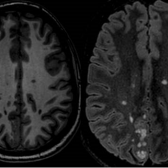

Sclérose en plaques